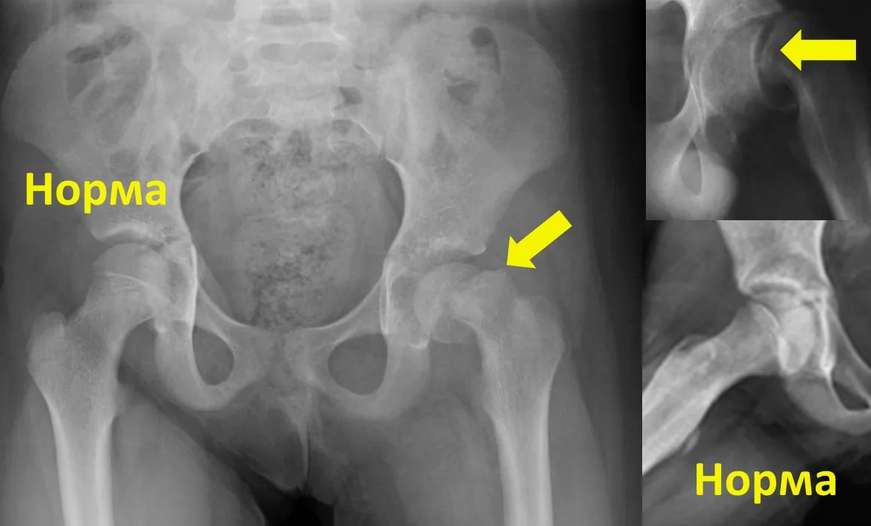

Рентген ТБС: Нормальные показатели